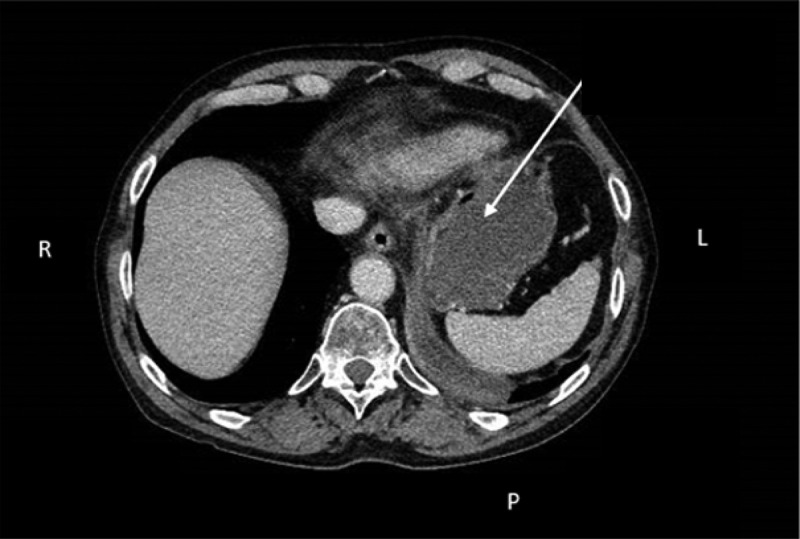

胰腺内镜超声引导细针穿刺活检(EUS-FNA)是许多内镜中心的常规检查项目,也是疑似胰腺癌诊断程序的一部分。由于经食道支气管镜超声引导细针穿刺活检术(EUS-B-FNA)能有效诊断纵隔和上腹部的病变,因此肺科医生对它的使用范围也大大扩展。下面的病例展示了 EUS-B-FNA 在一名患有非小细胞肺癌(NSCLC)和不明原因胰腺肿块的患者身上的安全性和可行性。一名曾被诊断为 NSCLC 的患者因怀疑 NSCLC 复发而被转诊至欧登塞大学医院呼吸内科。患者在同一手术中接受了支气管内超声引导(EBUS)-FNA检查,检查了多个疑似纵隔淋巴结,并对胰腺肿块进行了EUS-B-FNA联合检查。胰腺肿块和纵隔淋巴结的病理结果显示为鳞状细胞癌,由之前的 NSCLC 转移而来。我们在此证明,EUS-B-FNA 是一种可行且安全的技术,可用于从肺癌受检患者的胰腺病变中获取组织样本。

Endoscopic ultrasound-guided fine needle aspiration biopsy (EUS-FNA) of the pancreas is performed routinely in many endoscopic centers as part of the diagnostic set-up for suspected pancreatic cancer. The use of transesophageal bronchoscopic ultrasound-guided fine needle aspiration (EUS-B-FNA) by pulmonologists has expanded significantly, since it enables effective diagnosis of lesions in the mediastinum and upper abdomen. The following case demonstrates the safety and feasibility of EUS-B-FNA in a patient with non-small cell lung cancer (NSCLC) cancer and a pancreatic mass of unknown origin. A patient who was previously diagnosed with NSCLC was referred to the Department of Respiratory Medicine, Odense University Hospital due to suspected recurrence of NSCLC. The patient underwent endobronchial ultrasound guided (EBUS)-FNA from several suspected mediastinal lymph nodes and combined EUS-B-FNA from a pancreatic mass during the same procedure. Pathology results from the pancreatic mass and from the mediastinal lymph nodes showed squamous-cell carcinoma, metastasis from the previous NSCLC. We here by demonstrated that EUS-B-FNA is a feasible and safe technique to obtain tissue samples from pancreatic lesions in patients under investigation for lung cancer.